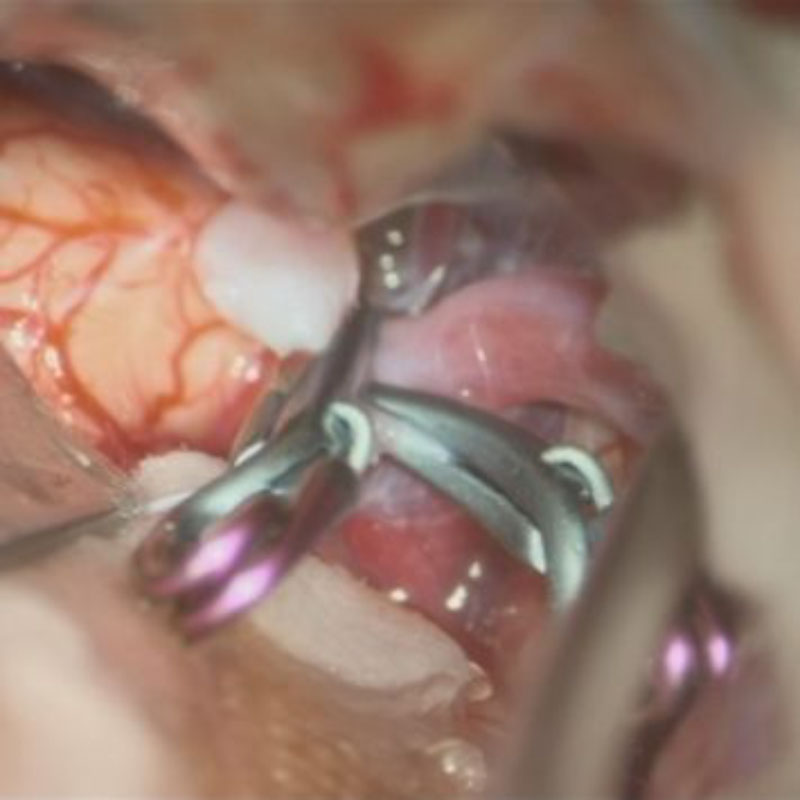

1

'26年1月

40代

右中大脳動脈瘤

クリッピング術

手術前

クリップ前

クリップ後

術後血管撮影